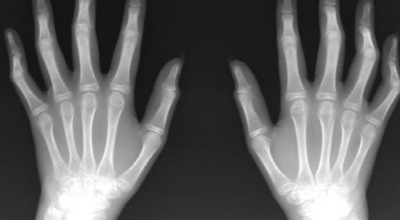

관절염은 크게 ‘퇴행성 관절염’과 ‘류마티스 관절염’으로 나눌 수 있습니다. 퇴행성 관절염은 손가락 관절의 연골이 닳아 뼈끼리 부딪히면서 마디가 튀어나오는 반면, 류마티스 관절염은 염증으로 손가락 마디가 붓고 튀어나오기 때문에 손 모양만으로는 정확히 구분하기 어렵습니다.

류마티스 관절염 초기증상 ⑤ 손 모양 변형

염증이 심해지면 관절 마디에 액체가 차거나 관절 조직이 증식하면서 마디가 부어오르게 됩니다. 염증이 계속되면 주변 근육과 인대도 약화되거나 손상될 수 있어, 손가락이 비틀리거나 변형되어 제대로 기능하기 어려워집니다.